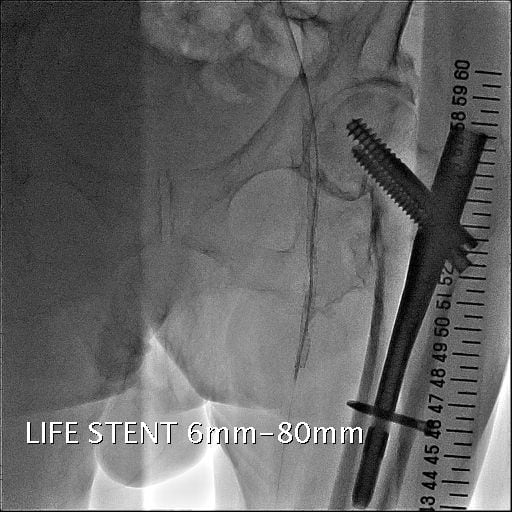

図5.SFAステント留置

SFAに径6mm、長さ80mmのステントを留置。